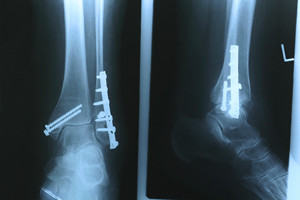

How Heel Pain Can Develop

Many people across the globe suffer from heel pain. It can occur from a variety of foot conditions, including plantar fasciitis, arthritis, or possibly from an Achilles tendon injury. There are patients who develop heel spurs, and the symptoms are often similar to those of plantar fasciitis, which can consist of heel pain in the morning after arising. If an injury has occurred, it may also result in a heel fracture. Common symptoms of this type of heel condition can include swelling, excessive pain, difficulty walking. There are many methods of treating heel pain, and it is strongly suggested that you consult with a podiatrist who can determine what the best healing technique is for you.

Causes of Heel Pain

Heel pain is often associated with plantar fasciitis. The plantar fascia is a band of tissues that extends along the bottom of the foot. A rip or tear in this ligament can cause inflammation of the tissue.

Achilles tendonitis is another cause of heel pain. Inflammation of the Achilles tendon will cause pain from fractures and muscle tearing. Lack of flexibility is also another symptom.

Heel spurs are another cause of pain. When the tissues of the plantar fascia undergo a great deal of stress, it can lead to ligament separation from the heel bone, causing heel spurs.

Heel pain should be treated as soon as possible for immediate results. Keeping your feet in a stress-free environment will help. If you suffer from Achilles tendonitis or plantar fasciitis, applying ice will reduce the swelling. Stretching before an exercise like running will help the muscles. Using all these tips will help make heel pain a condition of the past.